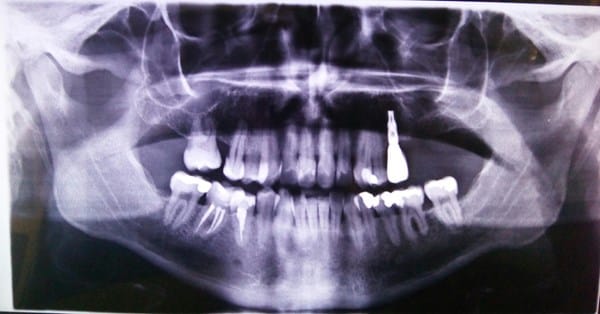

Esta es la primera radiografía después de hacerme las dos endodoncias.